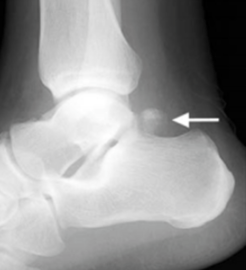

What is this?

Describe the epidemiology of Os trigonum?

Describe the pathophysiology of OS trigonium?

Name associated conditions of OS trigonium?

Describe the osteology of os trigonium?

Describe the symptoms of os trigonium?

What investigations are useful in Os trigonium?

What is the Differential dx of Os trigonium ?

What is the Tx of Os trigonium?